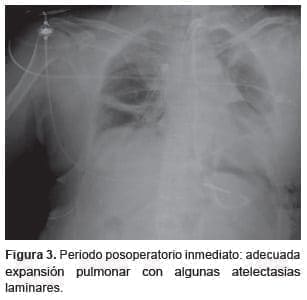

La evolución posoperatoria temprana fue satisfactoria (figura 3). El intercambio gaseoso fue óptimo y el índice PAFI (PaO2/FIO2) iba en ascenso; la saturación venosa de oxígeno y el lactato sérico eran adecuados, y hubo una disminución progresiva del flujo en la circulación extracorpórea; además, se logró una correcta restitución de la vía aérea, por lo que se decidió retirar dicho soporte en el periodo posoperatorio temprano y se continuó con asistencia respiratoria mecánica en modo protector, controlada por presión y con PEEP (Positive End Expiratory Pressure) baja, iniciándose posteriormente el destete del respirador según el protocolo.